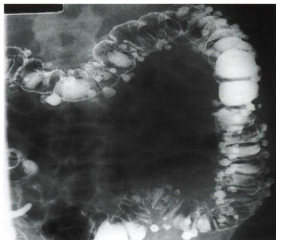

O enema opaco com duplo contraste ilustrado a seguir evidencia uma doença bastante prevalente. A respeito desta doença, assinale a alternativa

CORRETA

:

Raramente acomete o intestino delgado.